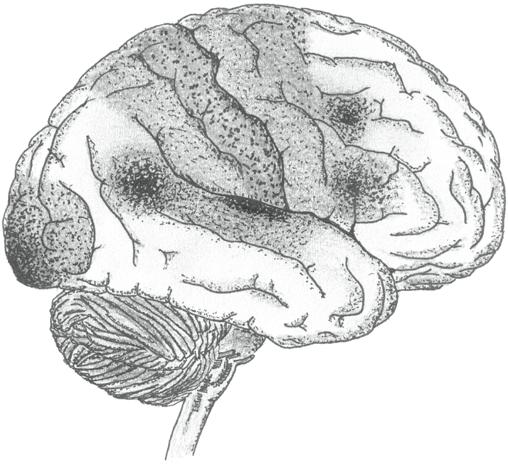

Centrální nervový systém je tvořen mozkem a míchou. Především mozek hraje u člověka dominantní a ústřední roli nejen v řízení všech funkcí tělesných, ale i psychických. Vstupuje do oblasti vztahové i přesahové. Je právem považován za nejsložitější orgánový systém v nám známém živém světě.

Složitá základní architektura mozku a z ní vycházející široké funkce jsou dány geneticky. Na výsledné stavbě a funkci mozku se však velkou měrou spolupodílejí i další endogenní (vnitřní) i exogenní (zevní) vlivy negenetické povahy působící nitroděložně, během porodu, po něm a prakticky po celý život.

Mimochodem i poruchy nervového systému, kterým se budeme věnovat v hlavní části naší knihy, mohou být podmíněny uvedenými vlivy – genetickými i negenetickými, endogenními i exogenními s tím, že původ některých chorobných stavů je nejasný a stále ho přesně neznáme.

Zejména v případě mozku platí, že stavba a funkce jsou navzájem podmíněny –určitá struktura je podkladem dané funkce a její realizace zpětně ovlivňuje jemnou mikroarchitektoniku mozku (a může ji do určité míry měnit).

Na komplexní provázanost stavby a funkce našeho mozku nikdy nezapomínejme a mějme neustále na paměti, že stavba našeho mozku podmiňuje naše aktivity a činnosti, jejichž realizace zpětně působí na mozek. Vše, co činíme (nebo co vnímáme a je nám činěno), má určitý potenciál měnit jemnou mikrostrukturu mozku a tím modifikovat naše chování a prožívání a nás samotné.

Vazba stavby a funkce mozku se v našich životech uplatňuje ve zdraví a funkčnosti i v nemoci a nefunkčnosti. Patří k aspektům vývoje a může se uplatňovat také v rámci léčby.

Nad složitou komplexností stavby, mnohostrannými funkcemi, efektivitou a výkonností i celkovou šíří vlivu lidského mozku nepřestáváme žasnout. Je to nepochybně právě náš mozek, který nás vydělil ze světa jiných tvorů a významně se podílí na všech aspektech našeho bytí (včetně prožívání, myšlení a konání).